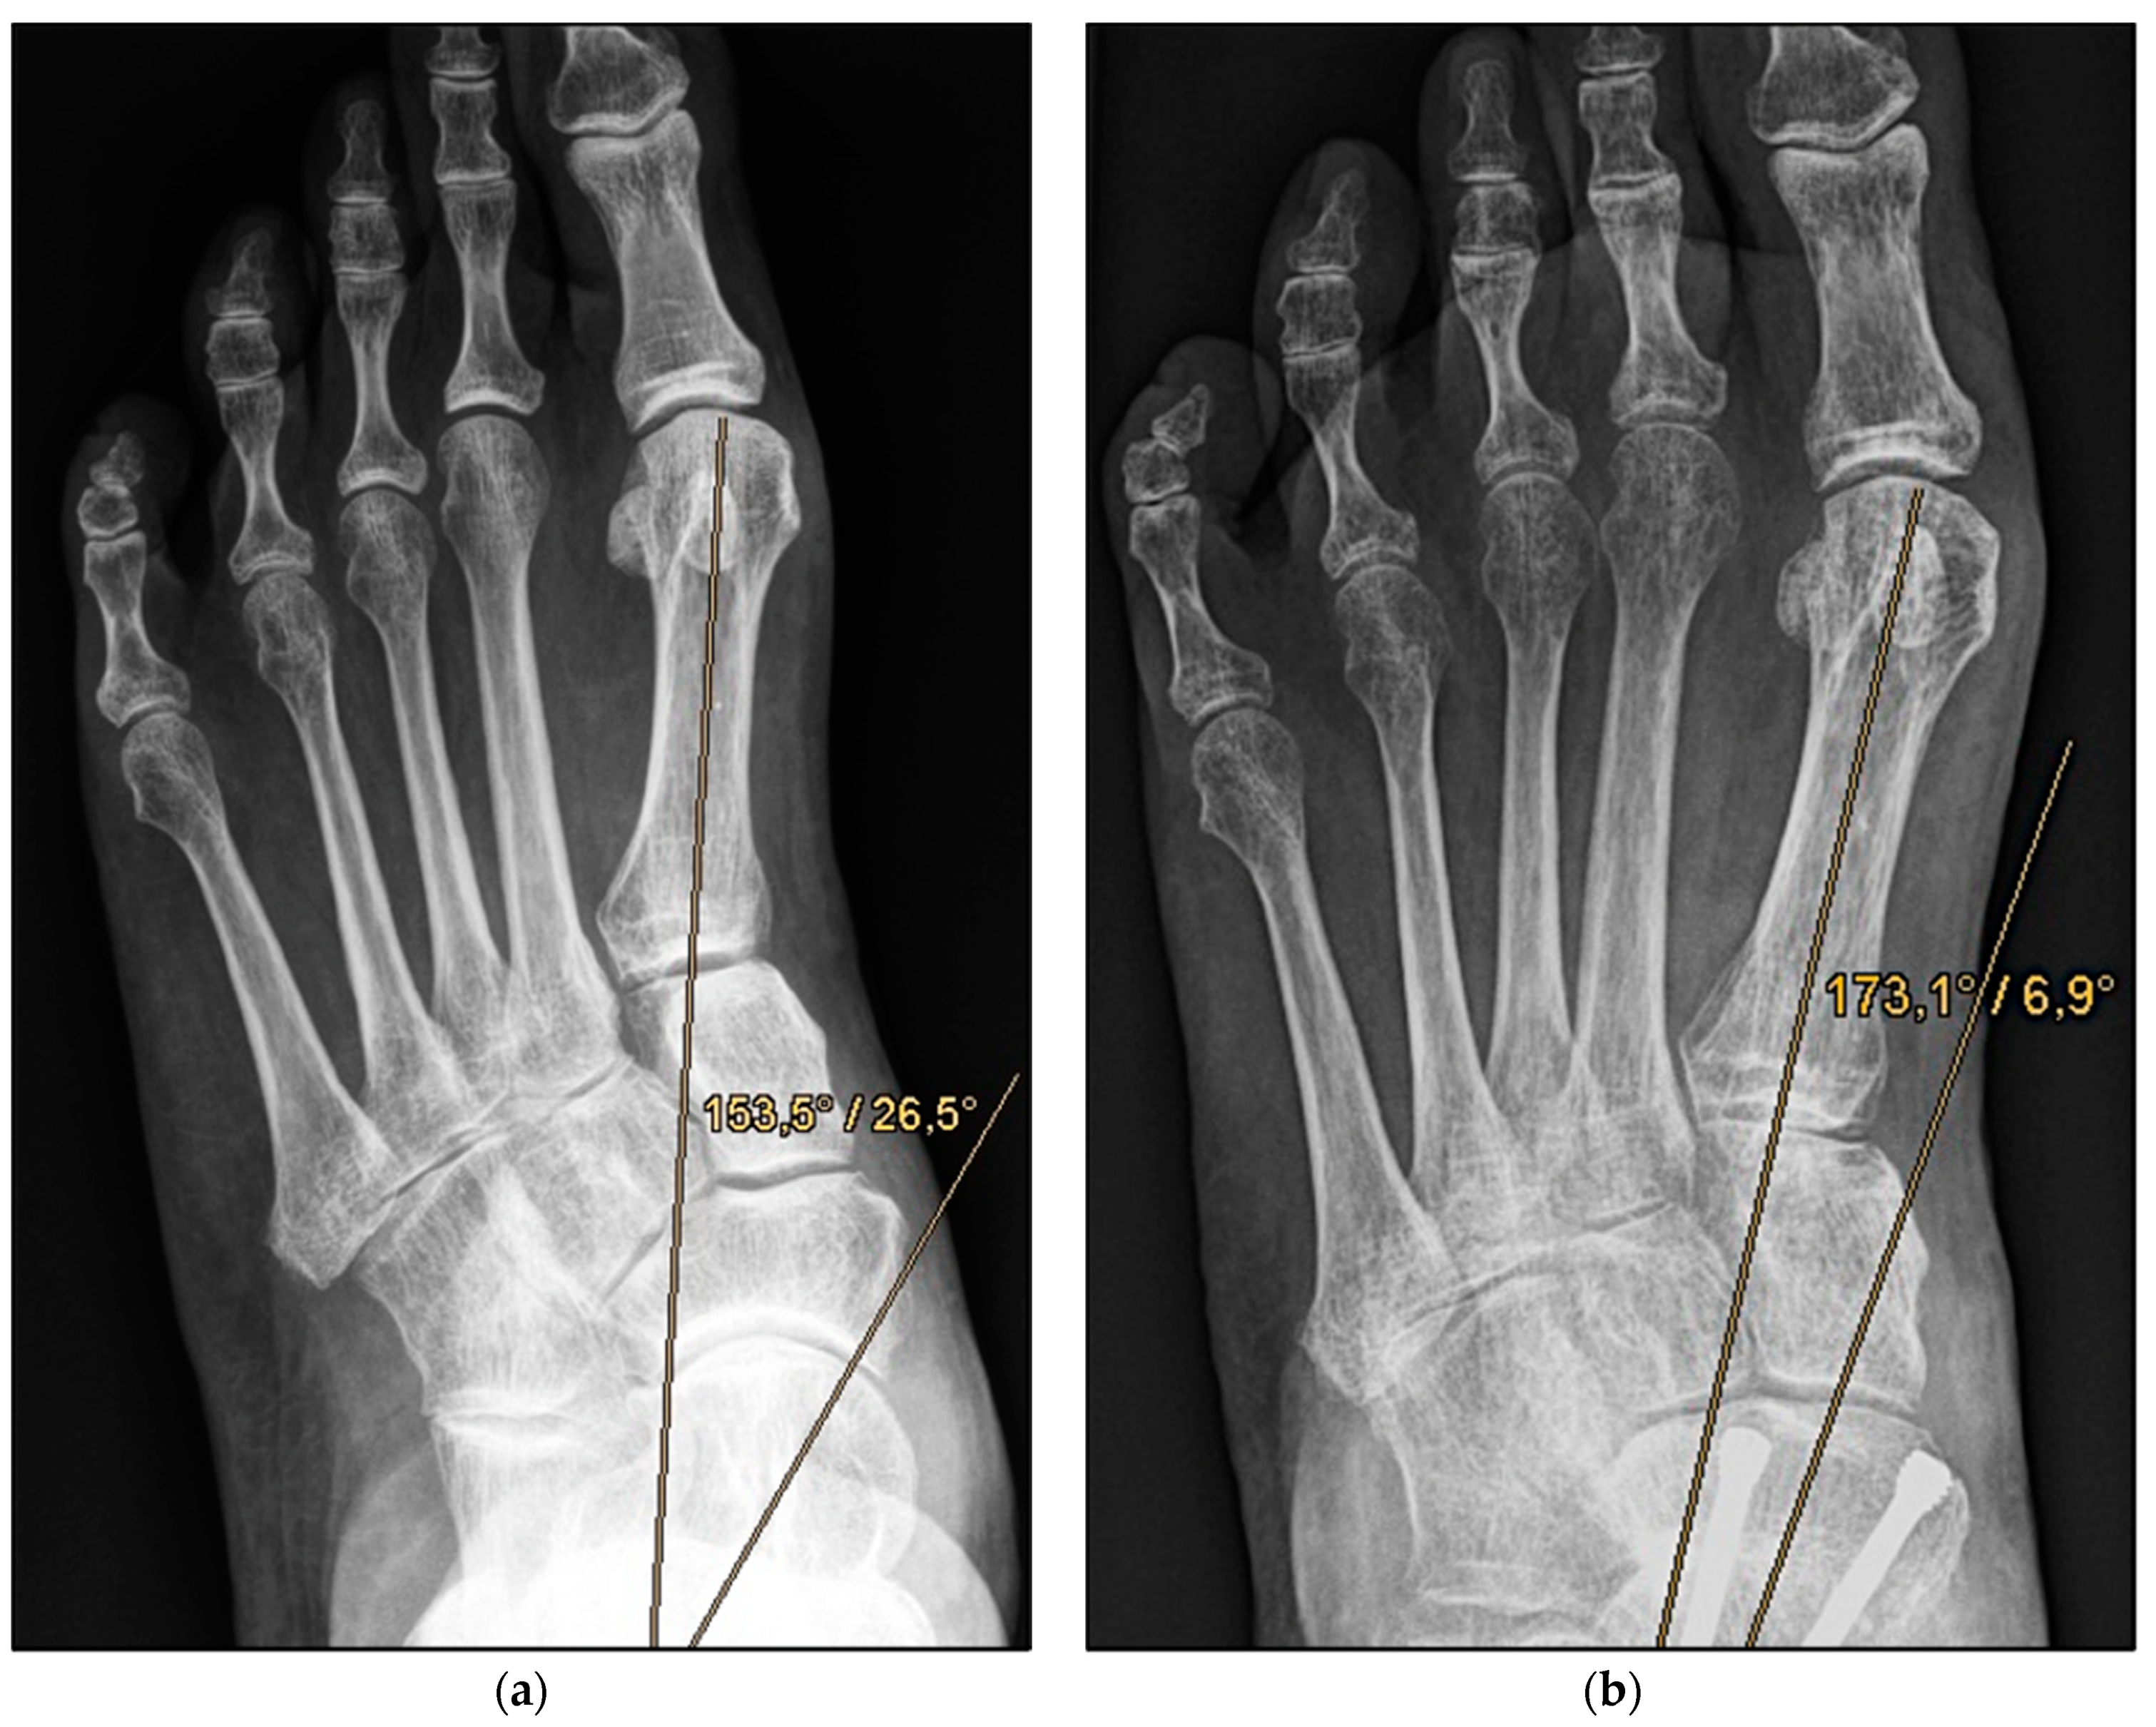

Figure 2.

Pre- and post-operative radiographic findings of combined talonavicular arthrodesis and calcaneal displacement osteotomy, left foot. (a) Anteroposterior view pre-operative, (b) anteroposterior view post-operative.

Figure 4.

Pre- and post-operative radiographic findings of double arthrodesis, left foot. (a) Anteroposterior view pre-operative, (b) anteroposterior view post-operative.

Medial calcaneal displacement osteotomy and talonavicular arthrodesis (Group A). In the first step, a V-shaped osteotomy was performed via an oblique approach to the lateral calcaneus with medial displacement of the back portion of the calcaneus. Osteotomy was performed using either an oscillating bone saw or bone chisel. Depending on the extent of the deformity, a medial displacement of approximately 8–10 mm was considered optimal. Fixation was achieved by means of two percutaneously inserted lag screws with diameters of 4.0–6.5 mm. The second step was talonavicular arthrodesis via a dorsal approach, usually with interposition of an iliac crest bone graft. Fixation was performed using two or three screws with diameters of 4 mm or a combination of screws and Nitinol compression implants (Figure 2a,b and Figure 3a,b).

Double Arthrodesis (Group B). Firstly, subtalar arthrodesis was performed via a lateral subtalar approach. Care was taken to ensure thorough resection of the articular surfaces and extensive release to achieve adequate correction of the valgus deformity and avoid the development of pseudarthrosis. Here, too, the insertion of autologous cancellous bone was considered obligatory. Fixation was achieved by means of two percutaneously inserted lag screws (diameter of 6.5 mm). The subsequent talonavicular arthrodesis was performed as previously described (Figure 4a,b and Figure 5a,b).